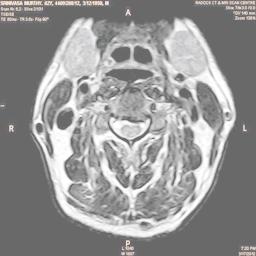

The developed algorithm presented in the previous section was coded using Matlab Version 8.0. The experiment was conducted by considering poor quality spinal cord images of having various lesions. The first column of Fig. 4 shows the axial view of neck spinal cord images of size pixels, respectively. The second column of Fig. 4 presents the same images enhanced using histogram equalization. As is evident from the results presented, the histogram equalization method performs global image enhancement operation which improves the contrast of an image but at the cost loss in image details. The third column of Fig. 4 shows the MSR based spinal cord image enhancement. It can be seen that from the result presented, MSR scheme improves the details that are not clearly visible in histogram equalization technique. In general, image enhancement achieved by MSR method is better compared to histogram equalization. However, the MSR method voilates gray world assumption. Therefore, the image enhanced by this scheme appears to be grayish. Although, numerous work have been reported for solving the problem due to gray world voilation, no work seems to developed for complete elimination.

The fourth column of Fig. 4 shows the image enhanced using Chao et al. []. It can be seen from the results presented that the reconstructed images of Chao’s method have black spots. The appearance of these dark patches degrades the visual quality of the enhanced image. The image enhanced using proposed multirate multiscale retinex image enhancement method presented in the fifth column of Fig. 4, overcomes the drawback of the Chao’s method. As we can see from the simulation results, image enhancement achieved by the proposed method has improved details with significant contrast enhancement. The enhanced images from the proposed method provides information to physicians, radiologists and researchers for various types of pathology detection.